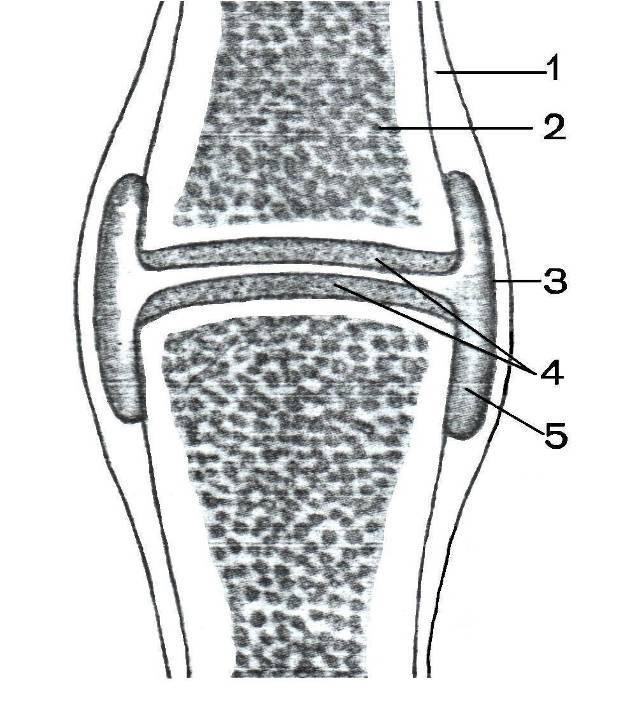

Рисунки Суставов: Анатомические Иллюстрации